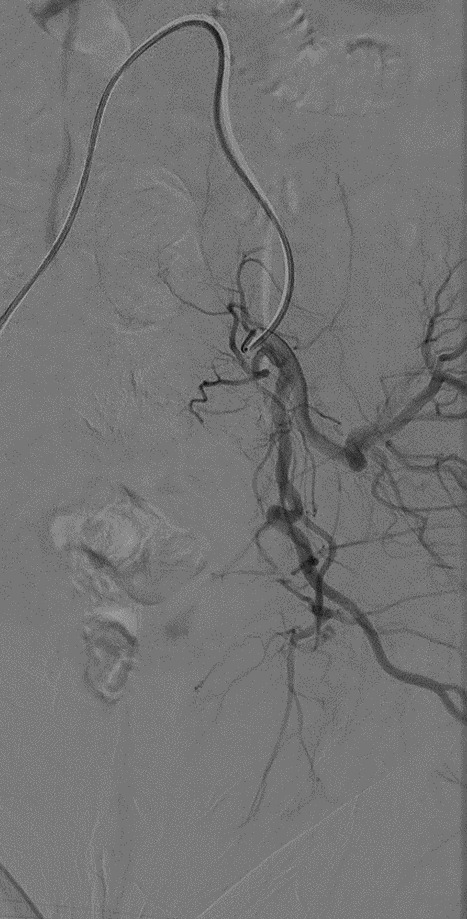

On POD #50 from the hysterectomy, the patient presented to the office with persistent vaginal cuff bleeding, less brisk than prior presentation. There were no sources of bleeding identified on exam. The patient then underwent a CT scan without any evidence of intraabdominal bleeding. Given persistent bleeding without a clearly identifiable source, the decision was made to proceed with bilateral embolization of the anterior divisions of the internal Iliac arteries. The embolization led to resolution of the vaginal cuff bleeding.

This patient’s localized labia minora pain was the result of nontarget labial embolization during bilateral internal Iliac artery embolization. The internal pudendal artery and uterine artery are adjacent to each other, branching off the anterior portion of the internal iliac artery. The internal pudendal artery supplies the labia minora. Most likely, injection of embolic material into the ligated uterine artery resulted in the reflux of particles into the right internal pudendal artery, producing ischemia in the branches supplying the labia.